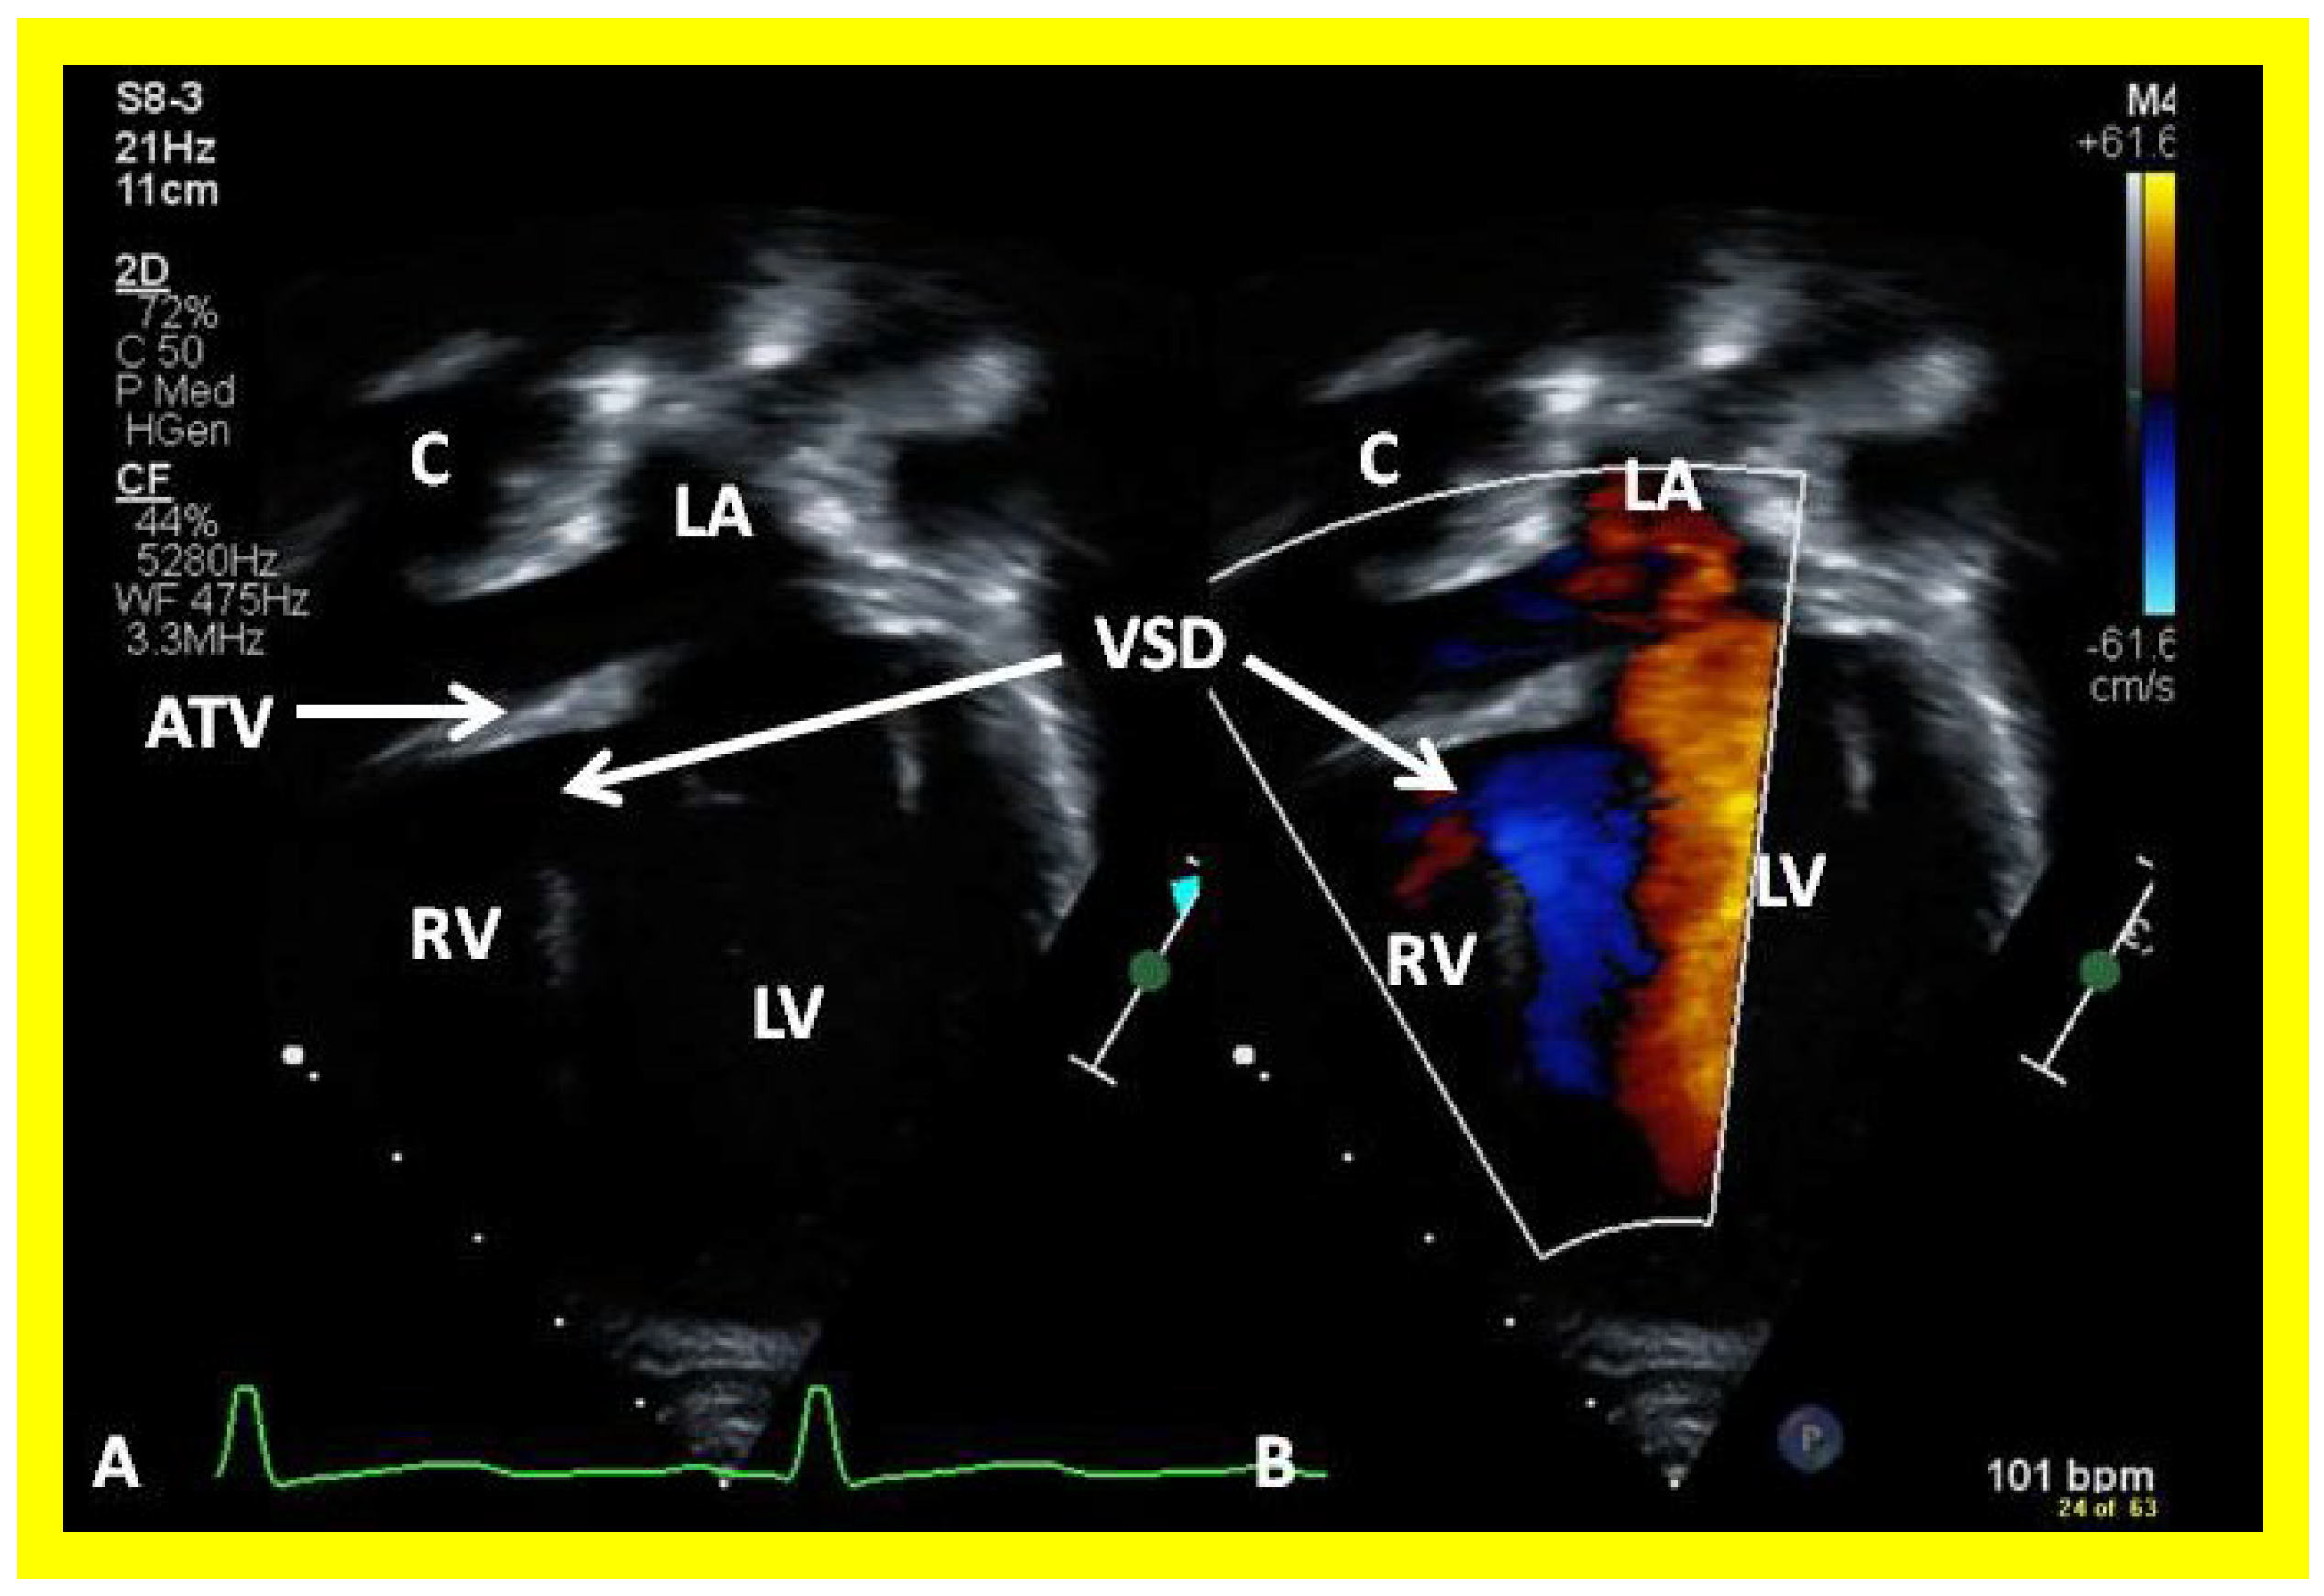

The relationship of the great arteries is examined next in order to classify them into various types, as mentioned above. The relationship of the great arteries (Figure 2, top) is established by following the vessels arising from the ventricles until the pulmonary artery (PA) bifurcation or aortic arch. In Type I patients with normally related great arteries, the aorta arises from the LV (Figure 10) and in Type II patients with transposition of the great arteries, the PA arises from the LV (Figure 11; Figure 12). In Type II patients, the blood vessel arising from the LV should be traced to demonstrate its branching into the right and left PAs (Figure 11; Figure 12). In Type III patients, it may be a little more difficult to assign the great artery relationship and, sometimes, other imaging studies, including angiography, may be needed to define the great artery relationship. In Type IV with truncus arteriosus, the limited data suggest that this can be performed by echocardiography (Figure 13; Figure 15). In the example shown [31], the atretic tricuspid valve (Figure 13a and Figure 14a), VSD (Figure 13b and Figure 14b), hypoplastic RV (Figure 14a), single vessel (truncus) arising from the heart (Figure 13c,d, and Figure 14c,d), and origin of the PA and its division into branch PAs (Figure 13d, and Figure 14c,d) were demonstrated.

Then, the ventricular septum is evaluated; the ventricular septum is intact in most Type Ia cases. In children with Type I (normally related great arteries), the VSD supplies the pulmonary blood flow (Figure 10) while in patients with Type II (transposition of the great arteries) the VSD allows the blood to flow into the systemic circuit (Figure 11; Figure 12). In Type I patients, the VSD is demonstrated by 2D (Figure 10A), and the left to right shunt across it by color (Figure 10B), pulsed and CW (Figure 10C) Doppler signals. The interrogation of the RV outflow tract and PA region should be performed; recording the peak Doppler flow velocity across the RV outflow tract and the pulmonary valve is helpful in identifying obstruction across these sites. The Doppler data from the VSD and RV outflow tract are also helpful in the estimating of PA pressures. In Type I babies, the 2D size of the VSD and the peak Doppler flow velocity across it are useful in quantifying the size of the VSD (Figure 10). The higher the VSD Doppler flow velocity, the smaller the defect. However, in patients with pulmonary hypertension or severe infundibular or valvar pulmonary stenosis, the VSD Doppler velocities are not reflective of the size of the VSD. Barring these exceptions, RV and PA systolic pressure may be estimated using a modified Bernoulli equation (RV/PA systolic pressure = systolic blood pressure – 4V2).

In Type II patients, the VSD may be small, causing obstruction to blood flow to the systemic circuit, and, therefore, the size of the VSD should be ascertained by 2D (Figure 11 and Figure 12), color Doppler (Figure 12), pulsed (Figure 15) and CW Doppler, as necessary. In these Type II patients, a high VSD velocity is indicative of subaortic obstruction. Interrogation of the LV outflow and PA region may reveal pulmonary or subpulmonary stenosis; the higher the velocity, the more severe is the obstruction. Studies from the suprasternal notch may show aortic coarctation (Figure 16), which is common in patients with Type II anatomy.

Figure 6. Selected video frames from apical four chamber, two dimensional echocardiographic views of a patient with tricuspid atresia showing an enlarged left ventricle (LV), a small right ventricle (RV) and a dense band of echoes at the site where the tricuspid valve echo should be (ATV) (thick arrow) with a closed (A) and open (B) mitral valve. A moderate sized ventricular septal defect (VSD) (thin arrow) is shown. LA, left atrium; RA, right atrium. Reproduced from Reference [29].

Figure 12. A selected video frame from a parasternal long axis view with color flow mapping of another patient with tricuspid atresia and transposition of the great arteries demonstrating the left atrium (LA), left ventricle (LV), a small right ventricle (RV) and a moderate sized ventricular septal defect (VSD). The vessel coming off the LV bifurcates into right (RPA) and left (LPA) pulmonary arteries. Reproduced from Reference [29]. PA, pulmonary artery.